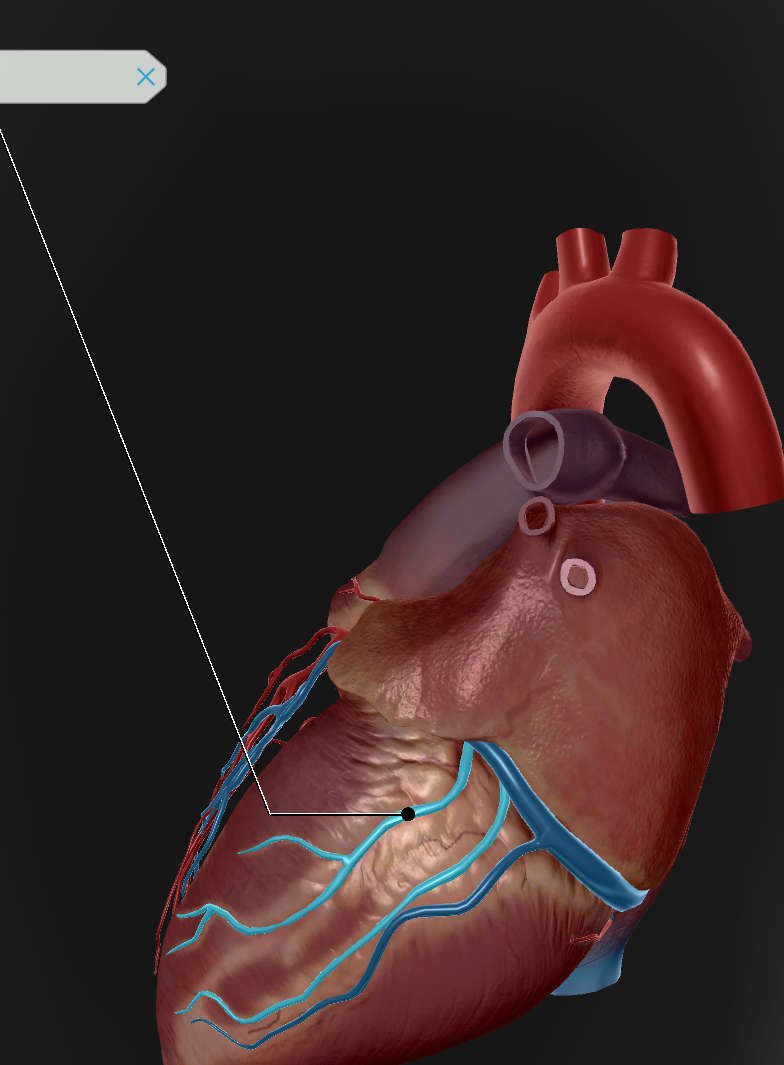

Anterior Interventricular Artery

Circumflex Branch

Coronary Artery

Middle Cardiac Vein

Coronary Sinus

Anterior Interventricular Sulcus

Coronary Sulcus

Small Cardiac Vein

Anterior Cardiac Vein

Posterior Interventricular Sulcus/Artery

Coronary Veins

Marginal Branch

Circumflex Artery

Great Cardiac Vein